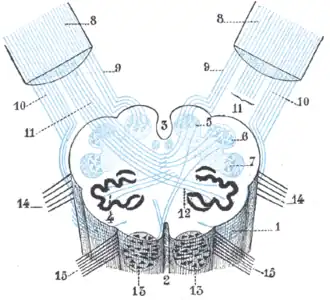

The external arcuate fibers wind across the lower part of the pyramid and olive and enter the inferior peduncle.

Diagram showing the course of the arcuate fibers.

Diagram showing the course of the arcuate fibers. -